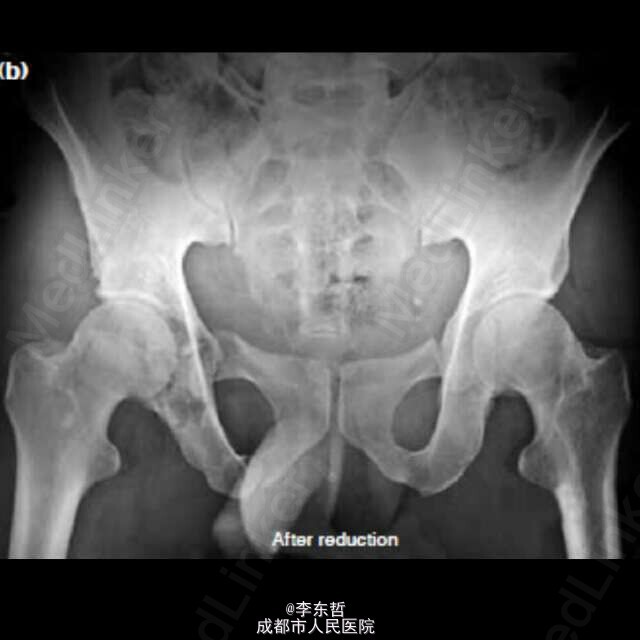

创伤性双侧不对称髋关节脱位很少见,该患者为31岁的男性,被一堵重约100公斤的墙砸伤于腰骶部,导致骨盆骨折、右髋关节后脱位及右髋臼的粉碎性骨折、左髋关节的前脱位